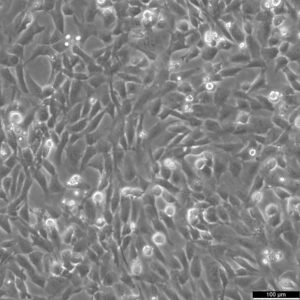

Morphology: Epithelial-like

Growth Properties: Adherent

Description: HuH7 was established in 1982 by Nakabayashi et al. from a 57-year-old Japanese male with well differentiated hepatocellular carcinoma.